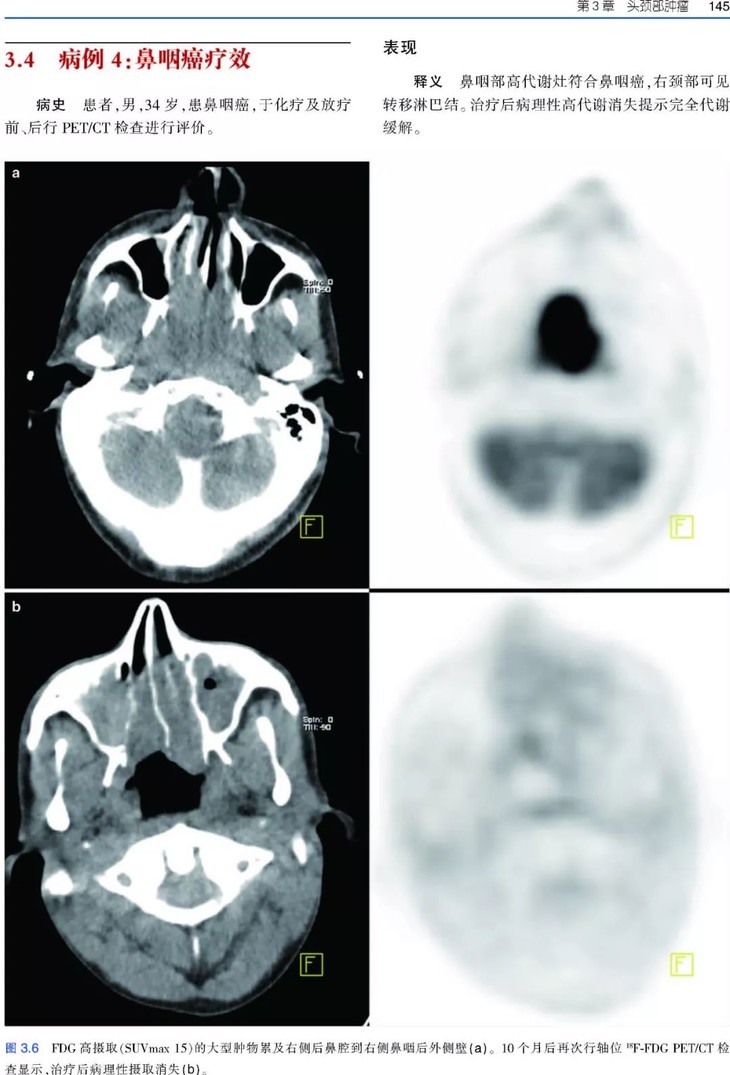

《肿瘤PET/CT成像图谱:病例解析》PET/CT扫描仪的出现,意味着功能代谢信息和解剖数据的融合,开创了医学领域的新纪元,特别是肿瘤学领域。自从PET/CT出现于研究中心,就成为肿瘤影像学中不可或缺的工具。《肿瘤PET/CT成像图谱:病例解析》涵盖了很多关于恶性肿瘤18F-FDG PET/CT诊断和治疗的临床病例。全书共两部分内容,第1部分为FDG PET/CT基础知识,包括18F-FDG的生理分布、正常变异、良性病变和技术伪影。第2部分涵盖了大量临床肿瘤病例,包括常见和罕见表现。每个病例都按照简要病史、影像表现描述、影像表现解释的顺序进行论述,最后是由相关文献支持的学习要点。本书中的所有病例均经组织病理学证实。本书适合核医学、放射学、肿瘤学、肿瘤放射学和核医学技术专业的住院医师和执业医师阅读。

• 涵盖全身各部位肿瘤的临床病例和大量PET/CT图像;

• 给出了影像诊断和鉴别诊断依据;

• 书中所有病例均经组织病理学证实;